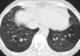

Cardiogenic pulmonary edema

Pulmonary edema is fluid accumulation in the tissue and air spaces of the lungs. It leads to impaired gas exchange and may cause respiratory failure. [Source: Wikipedia ]